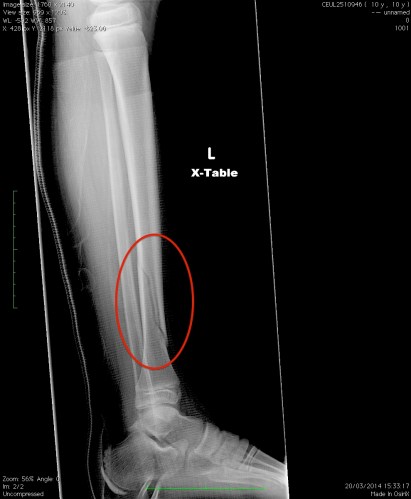

Lots of things have happened in that meantime, which is a good thing in a way, I suppose – it’s better than nothing! First and foremost, the biggest impact on my life has been Little Satis’ injury:

This happened shortly after his birthday, poor thing, when his grandfather and I took him skiing. It was only his second day on skis, and at the moment he claims it will be his last. It was a gentle slope with a curve, and he picked up a little too much speed (not a lot, honestly) and forgot to stop. The edge of the curve was bounded with a net, and when he hit it his ski twisted one way while the rest of him twisted the other. As you can probably see it’s a bad fracture, and he’s now in a full-leg cast for the next three months. Apart from the guilt and remorse, there’s a whole lot of inconvenience involved, especially since he can’t really get up the steep stairs to his bedroom. He’s been sleeping on the pull-out couch so far, which is getting in the way of just about everything. On the plus side, the pain seems to have more or less subsided for him, and he’s gotten pretty good on crutches.